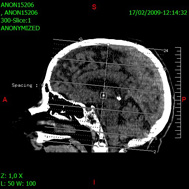

Examen TomoDensitoMétrique |

| Est devenu l’outil incontournable de toute exploration approfondie de l’organisme. La réception par des capteurs disposés autour du patient de rayons X traversant un organe permet d’obtenir une image en 3D. |